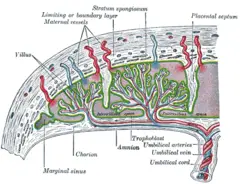

Maternal placental circulation

In preparation for implantation, the uterine endometrium undergoes "decidualization." Spiral arteries in decidua are remodeled so that they become less convoluted and their diameter is increased. The increased diameter and straighter flow path both act to increase maternal blood flow to the placenta. The relatively high pressure as the maternal blood fills intervillous space through these spiral arteries bathes the fetal villi in blood, allowing an exchange of gases to take place. In humans and other "hemochorial placentals," (see structure above) the maternal blood comes into direct contact with the fetal chorion, though no fluid is exchanged. As the pressure decreases between pulses, the deoxygenated blood flows back through the endometrial veins.

Maternal blood flow in humans is approx 600–700 ml/min at term.

Fetoplacental circulation

Deoxygenated fetal blood passes through umbilical arteries to the placenta. At the junction of umbilical cord and placenta, the umbilical arteries branch radially to form chorionic arteries. Chorionic arteries, in turn, branch into cotyledon arteries. In the villi, these vessels eventually branch to form an extensive arterio-capillary-venous system, bringing the fetal blood extremely close to the maternal blood; but no intermingling of fetal and maternal blood occurs ("placental barrier") (Schöni-Affolter et al. 2008).

Endothelin and prostanoids cause vasoconstriction in placental arteries, while nitric oxide vasodilation. On the other hand, there is no neural vascular regulation, and catecholamines have only little effect (Kiserud and Acharya 2004).